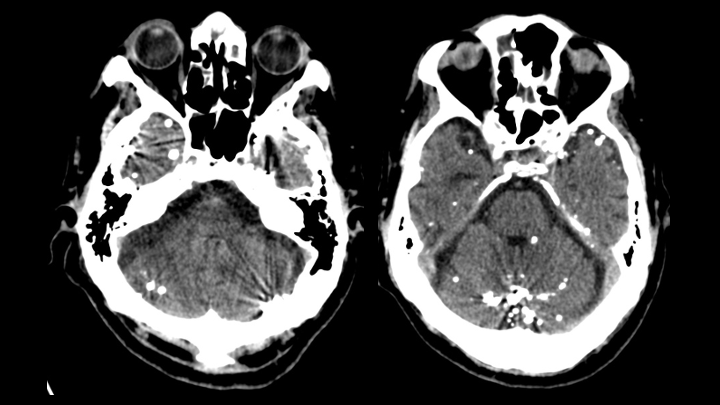

Se observan múltiples pequeños focos de material hiperatenuante dispersos en los espacios de circulación del LCR en la base del cráneo (localización extraaxial).

Se identifican múltiples pequeñas hiperdensidades intratecales, de tamaños variables.

El material presenta densidad metálica y genera artefactos en estría (streak artifacts).

CONTRASTE OLEOSO INTRATECAL ANTIGUO (diagnóstico más probable)

También conocido como Myodil, fue un medio de contraste a base de aceite (nombre genérico: iofendilato) que anteriormente se utilizaba para la mielografía.

Desde 1944, Pantopaque fue aparentemente el agente intratecal más popular, ya que permitía una buena reproducción de la imagen con adecuado contraste entre los diferentes elementos intratecales; sin embargo, pronto se descubrió que causaba aracnoiditis, aunque se mantuvo en uso clínico hasta 1986, cuando la Food and Drug Administration finalmente prohibió su comercialización en Estados Unidos debido a su lenta eliminación (1 mL/año) y su alta osmolaridad.